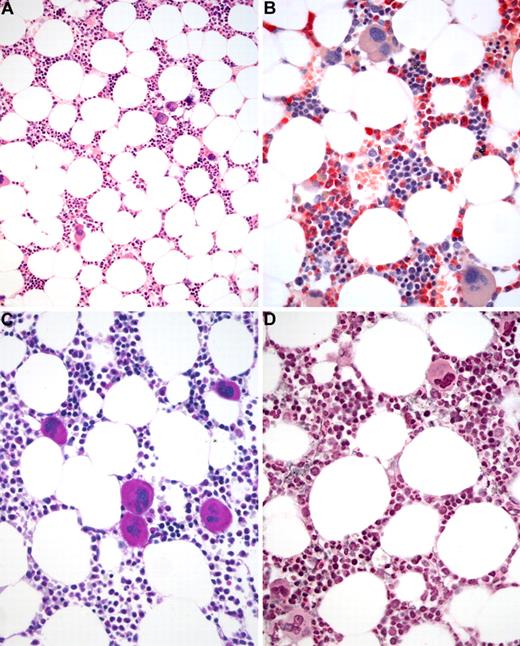

BM biopsy histology in ET in overview (×70) and low-power (×210) field. (A) Survey with hematoxylin and eosin-stained section shows an age-matched cellularity but prominent large to giant mature megakaryocytes in random distribution or loose clusters. (B) Chloroacetate esterase reaction demonstrates a normal amount and distribution of neutrophil granulopoiesis (red) and erythropoiesis besides the prominent megakaryocytes. (C) PAS staining reveals a hyperlobulation of megakaryocyte nuclei (almost staghorn-like) and mature cytoplasm without evidence of significant abnormalities. (D) Reticulin stain discloses no increase in fibers but large megakaryocytes. Images were acquired using Zeiss Axioplan 2, 10×/0.50 and 20×/0.50 EC PlanNeofluar.

BM biopsy histology in early PMF in low-power (×170) or medium-power (×350) field. (A) Survey with hematoxylin and eosin-stained section shows increase in age-matched cellularity and conspicuous clusters of atypical megakaryocytes. (B) Chloroacetate esterase reaction discloses that increased cellularity is mostly the result of neutrophil granulopoiesis (red) and prominent clustering of large, abnormal megakaryocytes with paratrabecular dislocation. (C) PAS staining reveals not only loose and tight clustering but also striking abnormalities of megakaryocytes showing large hyperchromatic-hypolobulated, cloud-like nuclei. (D) Reticulin stain displays minimal increase with a fine network of fibers between the clustered abnormal megakaryocytes. Images were acquired using Zeiss Axioplan 2, 20×/0.50 and 40×/0.60 EC PlanNeofluar.